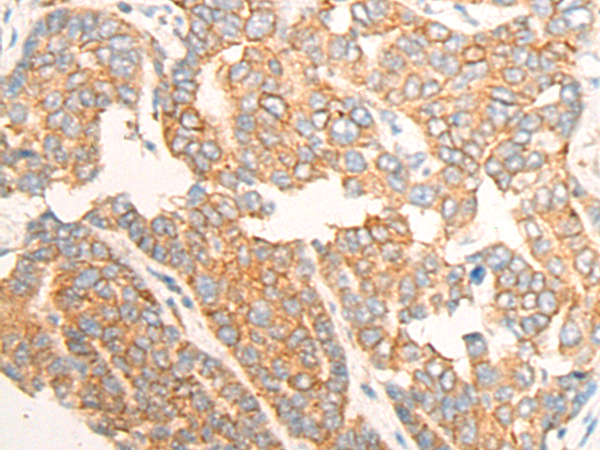

分类: 科研抗体货号: P13166别名: TIM3; CD366; KIM-3; TIMD3; Tim-3; TIMD-3; HAVcr-2应用: IHC反应种属: Human